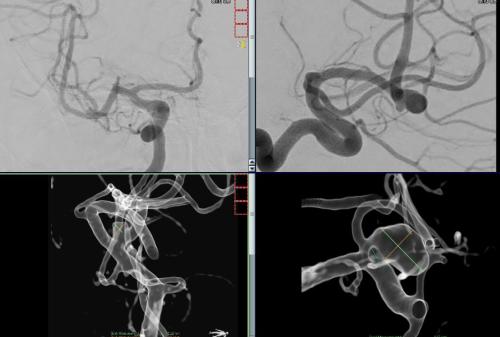

Aneurysma re. 7 mm Darstellung in einer DSA (digitalen Subtraktionsangiographie) links nur ein 2 mm „Baby-Aneurysma“ Im MRT war zuvor das linke Aneurysma aufgefallen, die Auflösung einer DSA ist technisch im MRT nicht erzielbar, beide A. liegen in der ACM Bifurkation jeweils, das re. Aneurysma wurde erfolgreich operiert, das linke Aneurysma wird kontrolliert.